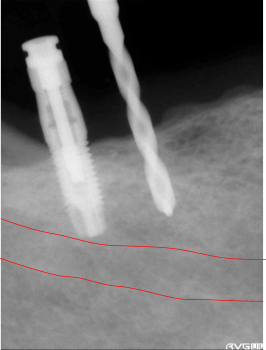

骨の深さが9mm程度だったので、ちょうど下歯槽管の真上ぐらいで止めます。 1本目終了。 |

最初に1.5mmのドリルで試し掘りした時の距離を変えずに2本目のインプラント終了。 骨に深さがなかったので、下歯槽管の真上まで植立。ドリルが1回転(360度)で1mm進むので、ドリルを180度回せば0.5mm、90度で0.25mmの精度で合わせる事が出来ます。